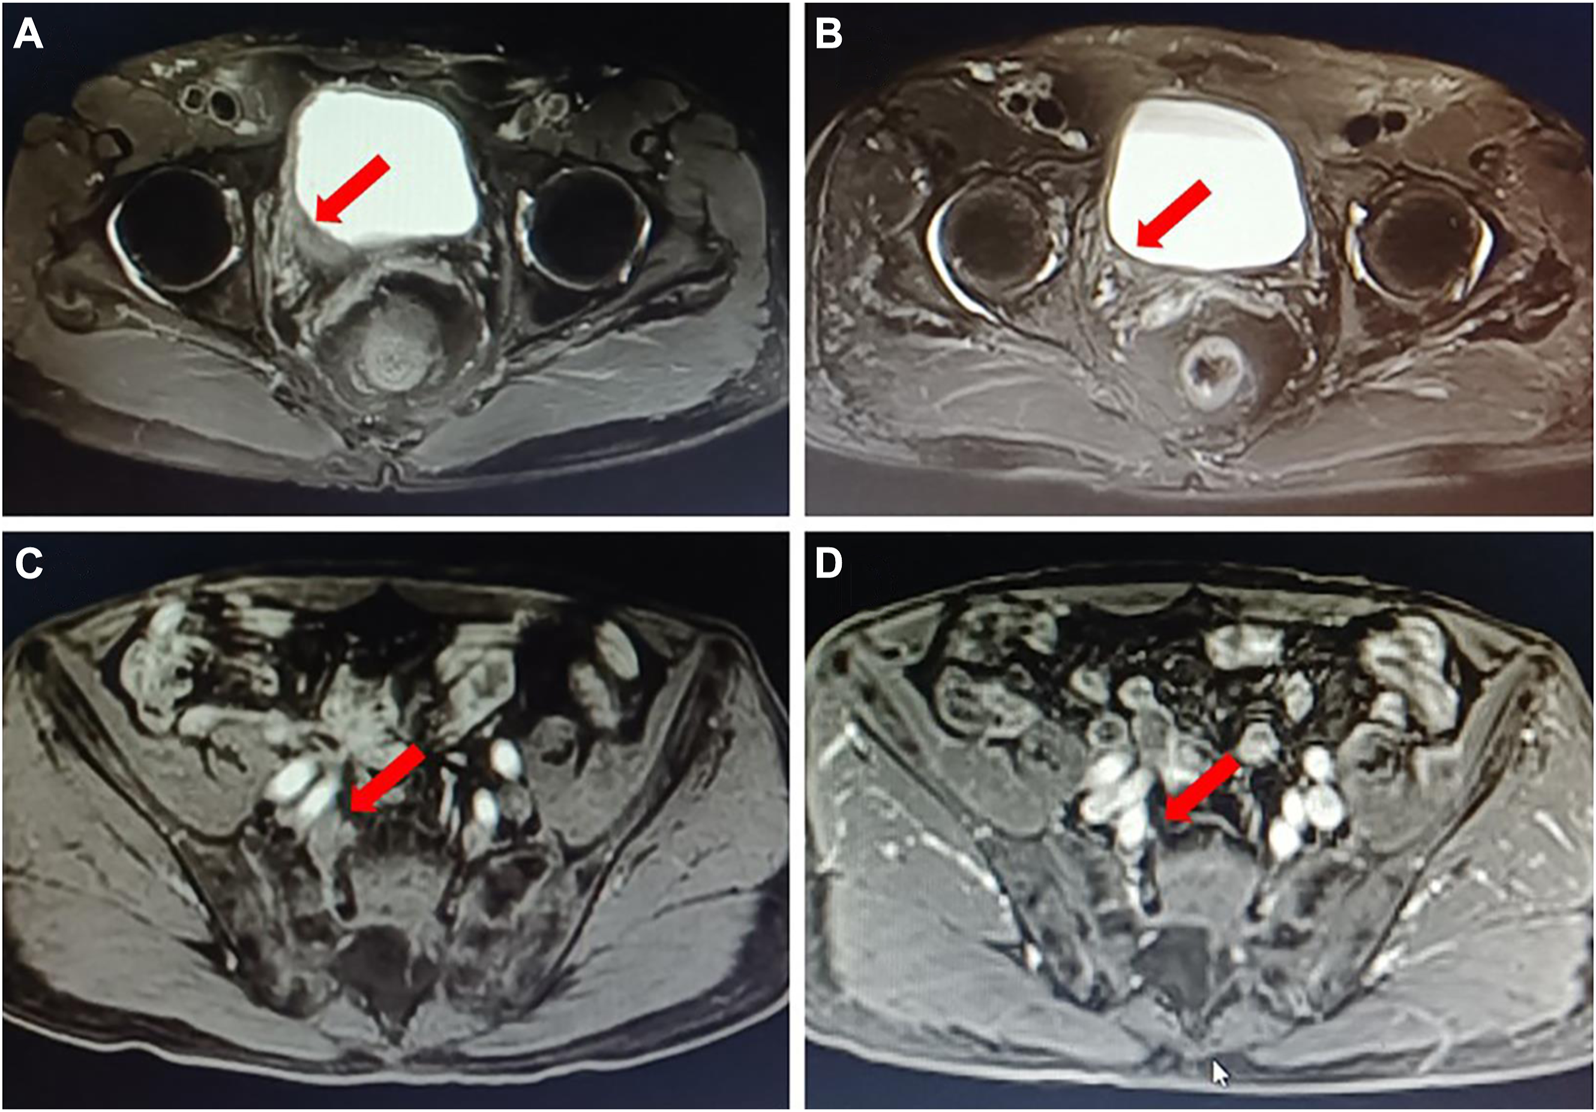

The treatment efficacy was finally evaluated by comparing imaging changes, urine cytological alterations, and results from transurethral resection. An ORR was achieved in eight cases, which included CR in five cases (Figure 1) and PR in three cases. rCR was entirely consistent with pCR.

FIGURE 1

A typical case of neoadjuvant therapy of DV in combination with an immune checkpoint inhibitor. A 72 years old male patient with “gross hematuria” was admitted; MRI showed that a bladder tumor in the right wall of the bladder with the inner segment of the right ureteral bladder wall involved (A); multiple mildly enlarged lymph nodes paravascular were found on the right iliac with a maximum of 1.1 cm, and lymph nodes metastasis were considered (C). Pathology of biopsy confirmed bladder high-grade urothelial carcinoma, with PD-L1 low expression (IHC) and HER2 (2+) (IHC). DV 2 mg/kg plus toripalimab 3 mg/kg, Q3w was given as neoadjuvant therapy for three circles. Then MRI was performed to evaluate the outcomes of the neoadjuvant treatment; it showed a radiological complete response (B, D). After laparoscopic right pelvic lymph node dissection with partial bladder incision and right ureteral bladder replantation, the postoperative pathology confirmed no evidence of cancer, suggesting a pathological complete response.